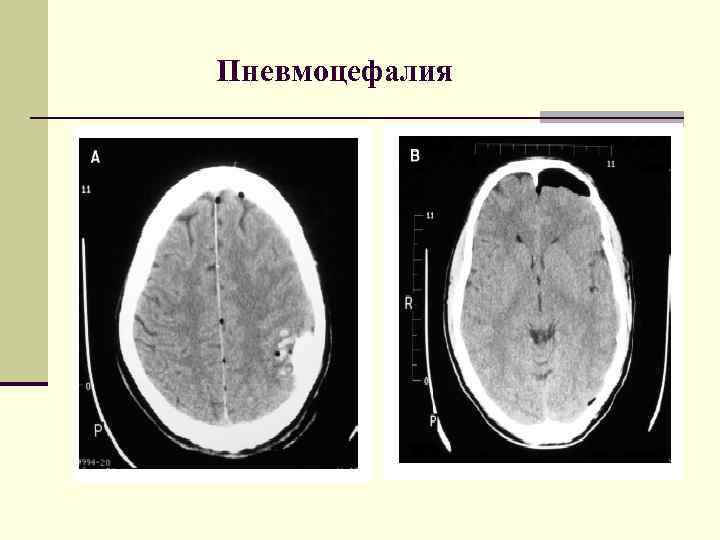

Пневмоцефалия Локальная (пневматоцеле), диффузная По локализации Субарахноидальная Внутрижелудочковая Субдуральная Эписубдуральная Паренхиматозная Пневмоцефалия Локальная (пневматоцеле), диффузная По локализации Субарахноидальная Внутрижелудочковая Субдуральная Эписубдуральная Паренхиматозная

Пневмоцефалия Пневмоцефалия

Пневматоцеле Контузионный очаг лобной доли Через 2 суток после травмы – формирование пневматоцеле Пневматоцеле Контузионный очаг лобной доли Через 2 суток после травмы – формирование пневматоцеле